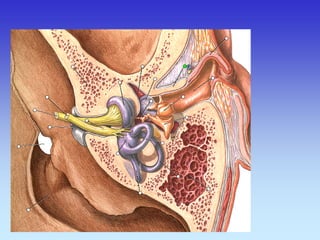

SLUŠNE KOŠĆICE

MALLEUS

INCUS

BAZA LUBANJE - CT

KANAL UNUTARNJEG ZVUKOVODA

KAROTIDNI KANAL

MALLEUS INCUS